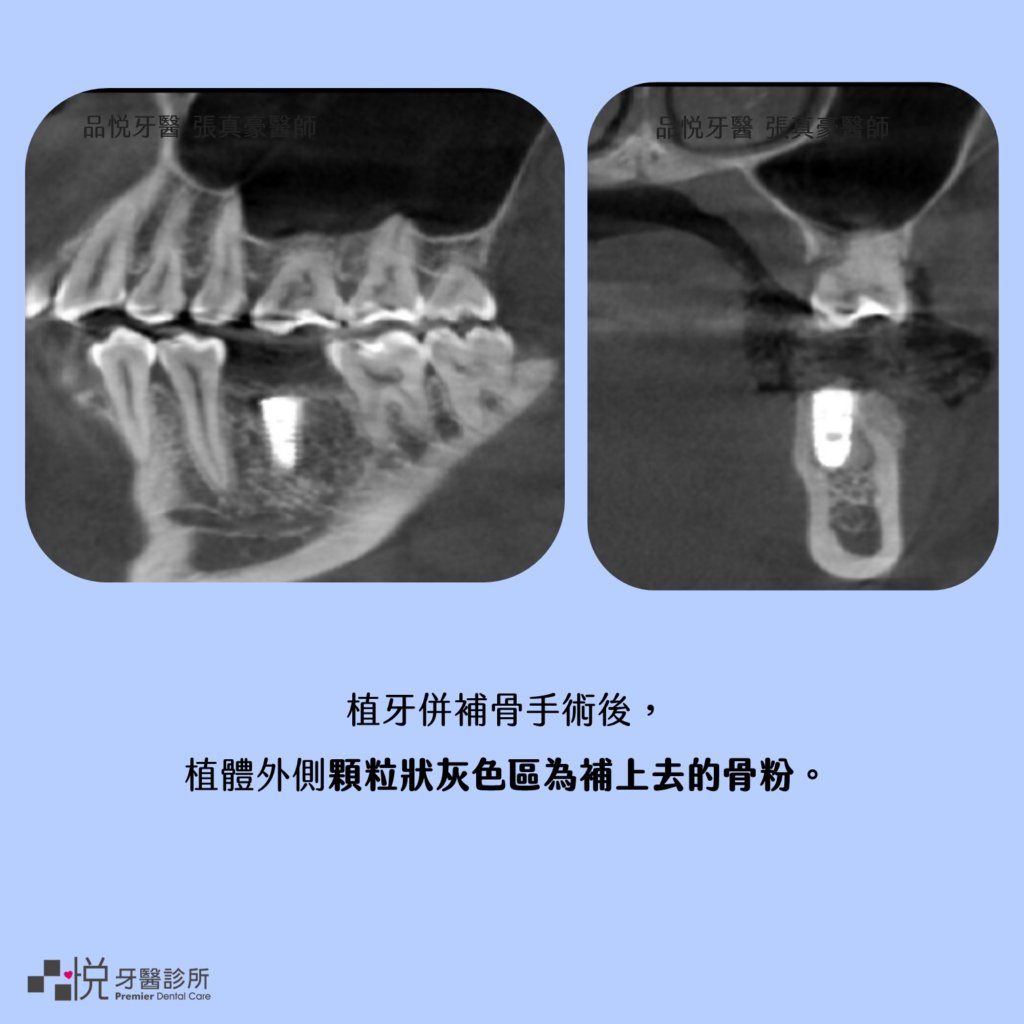

當術前評估發現骨量,可以容許穩定植入植體時,醫師可能會考慮植牙同時補骨,如此可以減少手術次數,通常術後半年後可以開始接植牙的假牙,完成植牙的療程。

以學理來說植體周圍有 1.5 mm 以上厚度的骨頭圍繞時比較能長期穩定使用,因此植牙時,往往需要補骨的步驟來達到理想的厚度。

當需要植牙時,需要有良好的齒槽骨及牙齦狀態,而當骨頭量不足時,醫師會使用骨粉以及再生膜讓骨頭量增厚,經過6個月到9個月骨粉會慢慢變成成熟的骨頭。